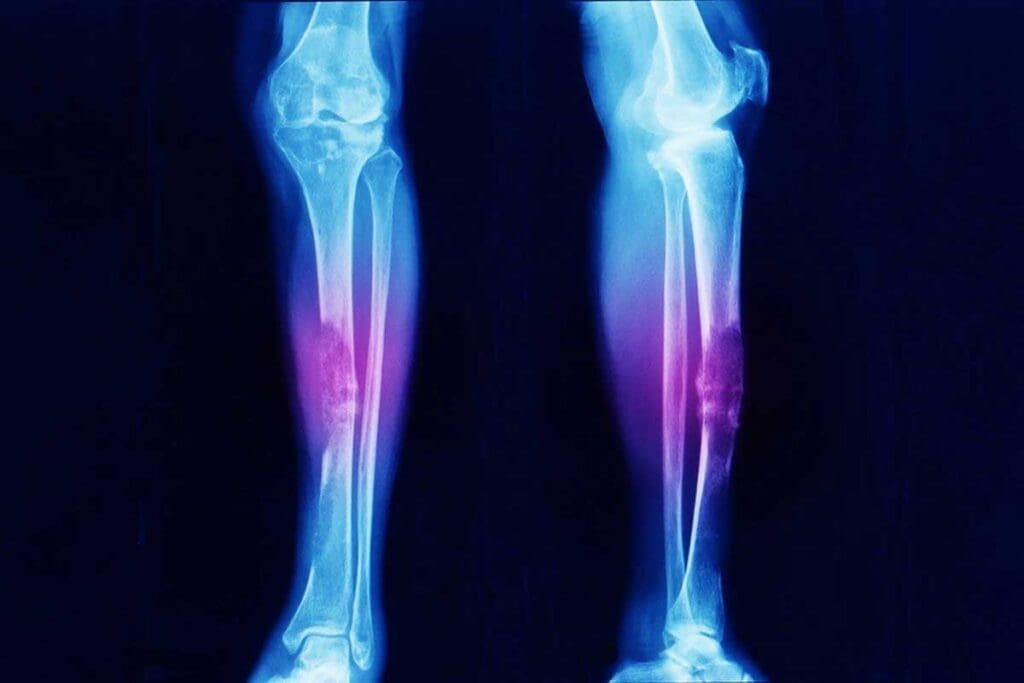

- The tumor often affects the long bones of the legs, pelvis, and chest wall.

Diagnostic Process and Workup

To diagnose Ewing sarcoma, doctors use many tests. These include X-rays, MRI, CT scans, and PET scans. They help find out the tumor’s size, where it is, and if it has spread.

Tumor Location and Size

The tumor’s location and size are key. Tumors in the pelvis or spine often have a worse prognosis. This is compared to tumors in other parts of the body.

Tumor size matters a lot. Bigger tumors are harder to treat. They also have a higher chance of coming back.